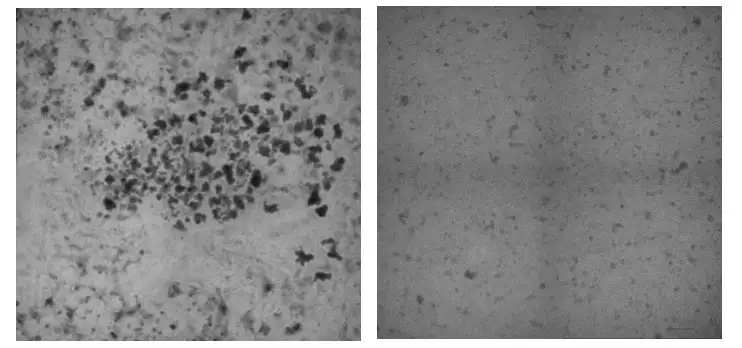

Given the right conditions, early-stage organoids called spheroids spontaneously form into 3D balls of cells. These get collected and transferred into a growth medium that provides the necessary signals for the cells to form into the specific cell types of a human organ—in this case the small intestine.

But the number of spheroids generated this way has proven inconsistent. The Cincinnati Children’s team determined it was possible to collect the unused precursor cell layer and use a centrifuge to drive cells into hundreds of tiny wells contained on small plastic plates. This prompts the formation of 3D cell aggregates that can be collected and used for organoid production.

Testing detailed in the paper shows that the spheroids made this way have no meaningful differences from those that grew spontaneously.

Next, the team placed samples of the precursor cells into freezers for storage. Once these cells were thawed and aggregated, they also formed viable spheroids.